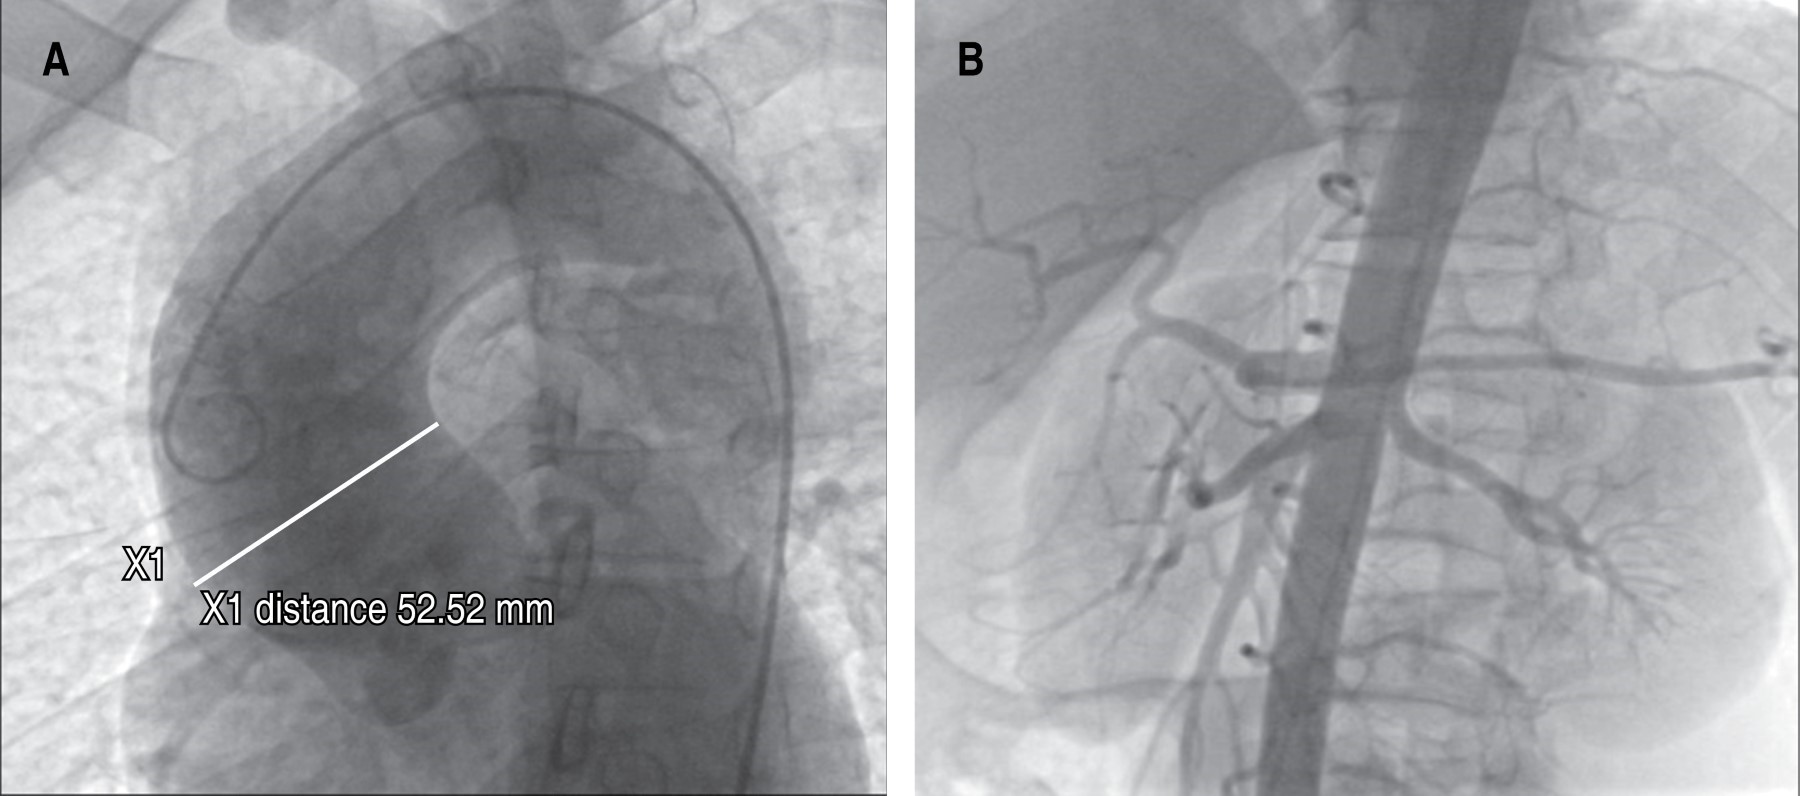

Figura 1

Figura 2

Figura 3